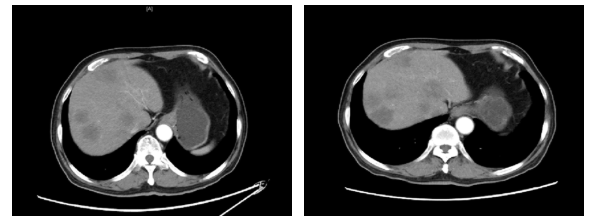

2019.11.18 腹部CT:肝脏多发结节(图2),考虑转移。

图2. 腹部CT(2019.11.18)

2020.1.5影像学评价:腹部CT:肝脏多发结节,较前增多增大,考虑进展(图3)。

图3. 腹部CT(左:2019.11.18,右:2020.1.5)